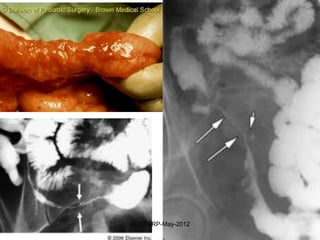

Repair

Although repair is a healing process, it may cause

tissue dysfunction

Examples:                      • Intestinal strictures

•   AS                         • Adhesions after

•   Healed MI                    surgery

•   Cirrhosis                  • Ankylosis

•   Contractures               • Cranial nerve palsies

after TB-meningitis

•   Corneal opacities

•   Pulmonary fibrosis

•   Bronchiectasis